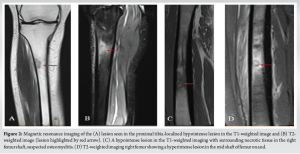

On the MRI, the patient had a hyperintense lesion in the mid shaft of the right femur with small intramedullary and subperiosteal collection on the T2-weighted imaging with hypointense lesion in the T1-weighted imaging, features suggestive of osteomyelitis. A second lesion hyperintense lesion on T2-weighted MRI was seen in the proximal tibia with a fracture line in the anteromedial cortex of proximal tibia of the right leg (unicortical), possibly osteomyelitis (Fig. 2).